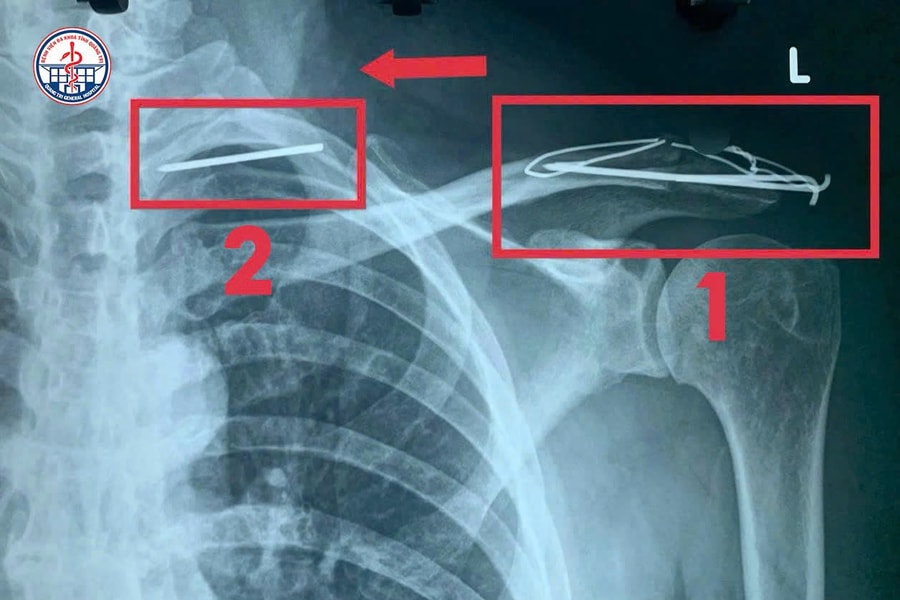

Hi hữu: Đinh phẫu thuật 'lang thang' trong lồng ngực bệnh nhân

Bệnh viện Đa khoa tỉnh Quảng Trị vừa tiếp nhận và điều trị thành công một trường hợp dị vật kim loại di chuyển vào phổi rất hiếm gặp, tiềm ẩn nguy cơ đe dọa tính mạng.